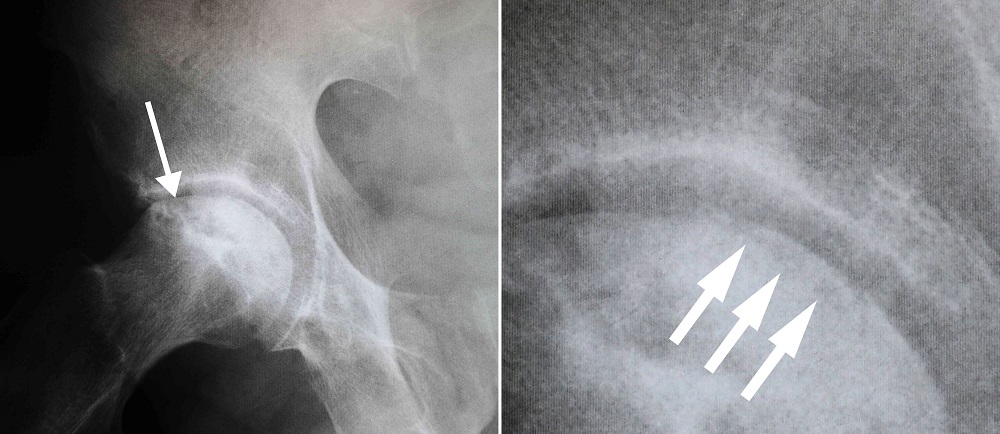

X-rays - X-rays provide images of dense structures, such as bone. X-rays are used to determine whether the bone in the femoral head has collapsed and to what degree. Osteonecrosis is typically seen as a wedge-shaped area with a dense whitish sclerotic border in the superior lateral portion of the femoral head. On lateral view, a lucent line called a “crescent sign” can often be seen just below the surface of the femoral head.

(Left) This x-ray shows osteonecrosis of the hip. (Right) When viewed close up, the x-ray reveals the “crescent sign” that is typically seen before collapse of the femoral head.